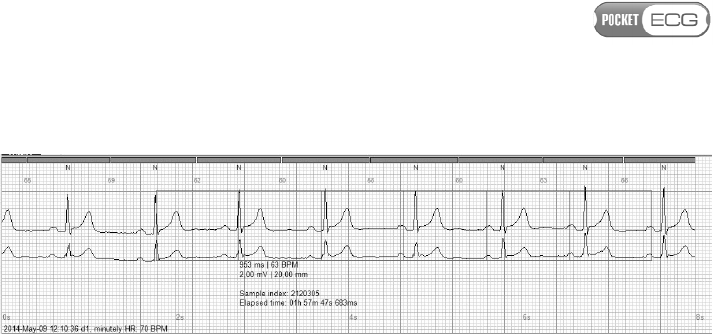

The PocketECG PC Client provides access to full disclosure ECG

Disclosure view of the PC client application, as shown in Fig. 25.

Fig. 25 Full Disclosure view

The timeline bar is displayed in the upper part of the screen. The user

may click on the timeline bar in order to navigate directly to any time

in the recording. The ECG waveform is displayed in normal size - as 8 s

strip in the upper part of the screen and as a miniaturized signal in the

bottom part of the screen (30 s of the signal in each row). User may

click on the miniaturized ECG and the corresponding full size strip will

be displayed in the upper part of the screen. The displayed strip is

Page 88 of 118

indicated by yellow frame highlighting the corresponding miniaturized

ECG fragment. The enlarged fragment of the Full Disclosure view

containing the ECG strip is presented in Fig. 26. The PocketECG

automatically detects and classifies QRS complexes. The annotations

for all detected complexes are displayed above the ECG beats (2). The

instantaneous heart rate is displayed between the ECG beat labels (3).

Fig. 26 ECG waveforms presented in the upper part of the screen